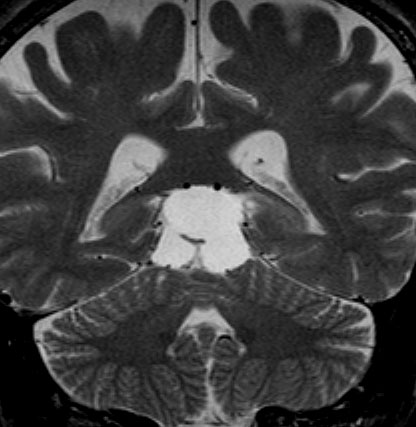

成人女性の松果体細胞腫で充実性腫瘍です。多少凹凸がありますがだいたい楕円形。中脳水道が閉塞して軽度の水頭症(頭の中に髄液が溜まる)になってきています。急性水頭症で急変して意識障害になることがありますので,迷わず摘出するか,第3脳室開窓術 ETVをしてから経過観察します。

これも偶然発見された無症状の女性の小さい松果体細胞腫ですが,ほとんど実質性でのう胞がありません。右はCISSという画像です。中脳の視蓋は圧迫されて変形していますが,中脳水道がまだ閉塞していないのがよくわかります。